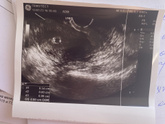

Девчули, пришел утром хгч…15 июля 2023 10:14 Девчули, пришел утром хгч… в разницей 4 дня…очень переживаю что может быть замершая Б, и читаю в интернете что хгч перестает расти или же постепенно снижается, у кого было что хгч слабо рос а Б нормально развивается? 1) сегодня 15.07 2) 10.07

13 июля 2023 15:23 Как и говорила 13 числа у меня запись к гинекологу, была удивлена от этого Узи. Нет никакой овуляции от прошлых узи, эндометрий уже лучше 9мм?, завтра хгч…планирую следующее узи в концу месяца, услышать сердечко. Я даже свой срок не знаю по хгч 322 4 … Читать далее

11 июля 2023 21:03 Добрый вечер девчули, с утра были адские боли в пояснице и низ живота болел…. Поехала в городскую больницу, на кресло не полезла сразу сказала…направила на повторное узи, по узи поставили срок 4-5 недель? прописали Дюфастон 2 р/д, эндометрий очень тонкий … Читать далее